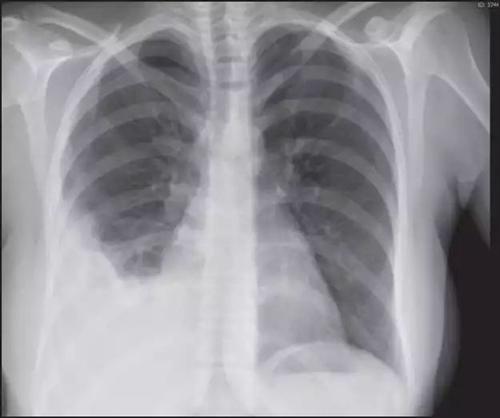

·胸膜炎是由于胸膜受到刺激而產生炎癥。那么,胸膜炎是怎么引起的呢?患上胸膜炎后,除了胸痛,還會出現哪些癥狀呢?接下來,我將詳細介紹胸膜炎的病因和癥狀。這就是我們所說的胸膜炎,也稱為內膜炎。

那么,胸膜炎是如何引起的呢?一般來說,有三種原因。生活中,不少人感冒后會出現胸痛、呼吸困難等癥狀,這可能是患上了胸膜炎。3.胸膜炎:胸膜炎指發生在胸膜腔的炎癥,主要與感染、自身免疫、惡性腫瘤等因素有關,可出現胸痛、胸膜等典型癥狀,且常在深咳嗽時出現,從而出現咳嗽心疼的表現。

咳嗽腋下痛是怎么回事咳嗽腋下痛可能是某些疾病的表現癥狀,如肺炎、胸膜炎、肋間神經痛等,應及時就診查明病因。胸膜炎的常見癥狀有哪些呢?謝醫師健康科普:常見癥狀:胸悶氣短、咳嗽、畏寒發熱。

·、外部創傷是胸膜炎最常見的原因。過敏反應或吸入性胸膜炎是過敏反應或吸入某些物質引起的。·第三、呼吸道刺激是引起胸膜炎的另一種原因。結核性胸膜炎是結核病中最為常見的一種類型,其癥狀包括氣短、咳嗽和發熱等。

2.胸膜炎:發生在胸膜腔內的炎癥,常以發熱、咳嗽、咳痰、胸痛、胸悶及呼吸困難為主要臨床表現,也可能出現腋下痛。咳嗽心疼是怎么回事咳嗽心疼可由生理因素、心絞痛、胸膜炎等因素引起。

能夠引起胸痛的原因有很多,如胸膜炎、肺膿腫、肋軟骨炎癥、心包炎、心絞痛、心梗等。除肺炎外,一些其他疾病也可以引起咳嗽伴咳白痰癥狀,例如慢性支氣管炎、間質性肺病、支氣管哮喘、胸膜炎、肺癌等,因此僅憑癥狀無法明確診斷,需要完善胸片、ct、血常規、痰培養等相關檢查化驗進一步明確診斷。

胸膜炎是呼吸系統的一種疾病,常見于年輕人群,多發生在冬春季節。感染性心包炎能自愈嗎?感染性心包炎一般不能自愈,感染性心包炎有以下幾種類型:1、病毒性心包炎:病毒感染者多在感染癥狀出現前10-12天有胸痛等癥狀,部分病人可伴有肺炎和胸膜炎的臨床表現,可以出現少量心包積液;2、結核型心包炎:有原發性結核的表現,較少有發熱、胸痛等,可能有較多的心包積液,積液中有時能找到結核分枝桿菌;3、化膿性心包炎:有原發感染病灶或敗血癥的表現,患者通常有高熱、胸痛,白細胞計數明顯增高,中性粒細胞計數也明顯增高,心包積液較多。